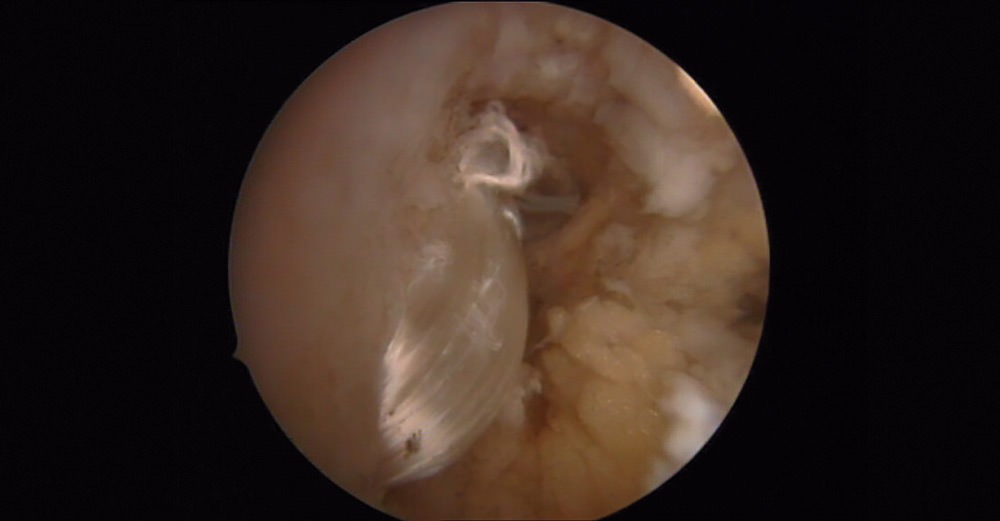

Una vez tratadas el resto de las patologías, con la cámara en el portal anteromedial y los instrumentos por el anterolateral, realizamos una limpieza con motor y vaporizador de todas las adhesiones, sinovitis... que podemos encontrar en el receso lateral y las cuales nos podrían dificultar la manipulación de la plastia.

En las artroscopias, en todos los casos se observó una rotura completa del LPAA con presencia de fibras del ligamento en diferentes fases degenerativas.

En los 20 casos se identificó sinovitis anterolateral y se realizó exéresis de la misma.